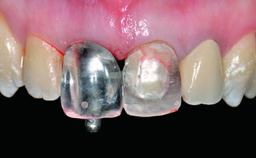

Replacement of an Ankylosed Upper Left Central Incisor: Bone Augmentation and Socket Grafting, Late Placement of an RC Bone Level Implant

A 15-year-old male patient was referred to us by his pediatric dentist in June 2004 for evaluation of treatment options for his failing tooth 21. The patient had recently seen an endodontist for internal bleaching and been advised that there had been significant resorption and ankylosis. The patient’s mother was concerned because the tooth appeared shorter than the adjacent one. His past dental history was significant for trauma (September 2001), where the tooth had been avulsed and reimplanted. Teeth 11 and 21 had been endodontically treated.